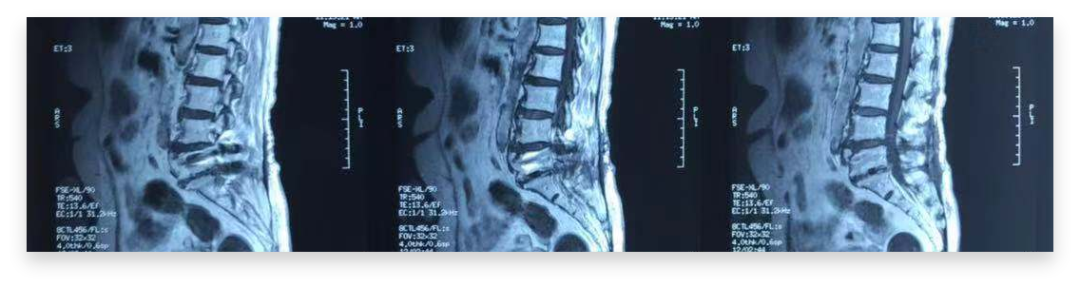

♦ 影像学检查:

腰椎平片示:腰椎术后改变。

腰椎MRI:腰5/骶1左侧椎间孔纤维黏连,腰椎退行性改变。